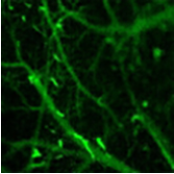

在腦血管研究中,通過對不同近紅外稀土熒光探針進(jìn)行功能化修飾,團(tuán)隊(duì)*區(qū)分了活體小鼠腦部血管網(wǎng)絡(luò)中的各級血管。利用激素刺激小鼠模擬神經(jīng)對血流的調(diào)控作用,在不開顱的情況下,實(shí)現(xiàn)了對小鼠動脈血管舒縮運(yùn)動的實(shí)時動態(tài)監(jiān)測,為血液動力學(xué)研究提供了*信息。

圖3:小鼠腦血管顯微成像

在免疫反應(yīng)研究領(lǐng)域,團(tuán)隊(duì)利用*近紅外稀土熒光探針特異性標(biāo)記小鼠的中性粒細(xì)胞,實(shí)現(xiàn)了在單細(xì)胞水平上對免疫反應(yīng)的實(shí)時動態(tài)監(jiān)測。能夠清晰觀察到單個中性粒細(xì)胞在皮下炎癥部位及腦損傷部位趨化性、外滲、激活等過程,避免了傳統(tǒng)成像方法開辟視窗對觀測結(jié)果的干擾,為深入了解細(xì)胞免疫反應(yīng)機(jī)制提供了全新思路。